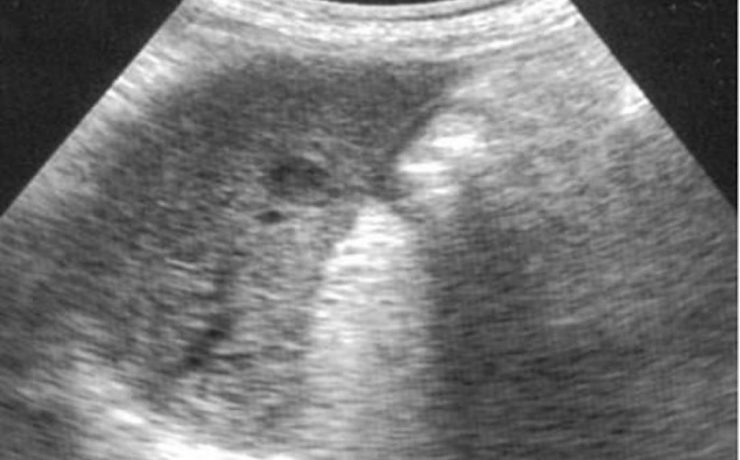

Durante el embarazo y la lactancia, la mama puede verse afectada por una variedad de trastornos únicos y específico, incluyendo trastornos benignos, relacionados con los cambios fisiológicos, inflamatorios, enfermedades infecciosas, papilomatosis juvenil y tumores benignos y malignos. Pacientes con carcinoma de mama asociada al embarazo presentan diagnóstico de neoplasias avanzadas y